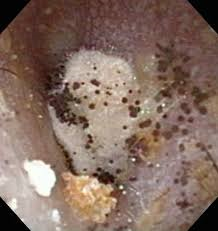

これはカメラでのどの上の方から見ている画像なので、わかりにくいかもしれませんが...(^-^;

こんな感じで白いものがのどに点々とつくことが多いです。

この画像では咽頭から喉頭(のどの奥)までカンジダを認めます。

進行するとこの白いものが取れにくくなったり、出血しやすくなったりもします。